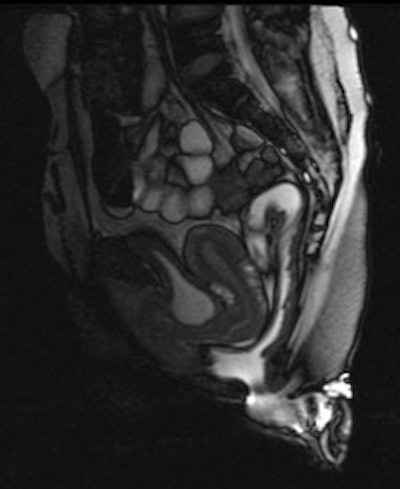

Left: MR image obtained at rest, after rectal filling with gel; normal values of anorectal angle and anorectal junction, with respect to the pubococcygeal line. Right: MR image obtained during straining and evacuation: A large anterior rectocele develops, associated with descent of the posterior pelvic floor. Images courtesy of Dr. Francesca Maccioni.While the examination is neither painful nor particularly disturbing, Maccioni believes that possible causes of discomfort may be related to claustrophobia, the use of a rectal contrast medium, and attempting tricky maneuvers under unfavorable conditions. It can be difficult, in a closed magnet unit and in the supine position, to attempt functional maneuvers, and sometimes this may be unhygienic, she added. MRI techniques should be further developed to reduce possible discomfort, and her suggestions for doing this include thorough explanations to patients about the procedure. It is critical because the success of dynamic MRI derives from the effectiveness of the maneuvers performed, she stated.